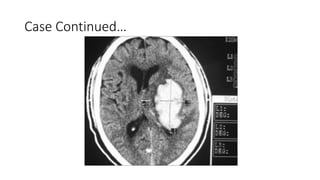

Case 1

50 year old man presents to ER with

sudden onset severe headache.

PMHx

1. Atrial fibrillation

Medications

1. Warfarin 5 mg PO daily

2. Metoprolol 25 mg PO BID

Investigations

• Hemoglobin 9 g/dL

• Platelets 200 x109/L

• WBC 9 x109/L

• INR 13

• aPTT 38 s

• Electrolytes, renal, and liver

function normal

Case Continued…